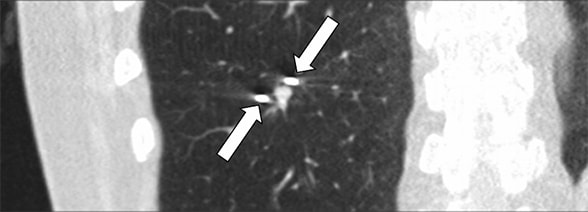

Axial CT image showing right lower lobe nodule

Axial CT image showing right lower lobe nodule

Axial CT image showing a 7-by-5-mm right lower lobe nodule (arrow) that lies immediately adjacent to a vessel and an airway.

CT-guided cryoablation of lung nodule

CT-guided cryoablation of lung nodule

CT-guided cryoablation of the 7-by-5-mm lung nodule. Two cryoprobes (arrows) are seen on each side of the nodule.

Biochemical evaluation confirmed corticotropin (ACTH)-dependent Cushing syndrome. Pituitary-directed MRI demonstrated a normal pituitary gland, and inferior petrosal sinus sampling indicated a nonpituitary source of ACTH secretion. In search of an ectopic neuroendocrine tumor, a chest CT scan identified a 7-by-5-mm nodule in the right lower lobe.

Additional findings included hypertrophied bilateral adrenal glands but no other foci of potential disease. Notably, both 18F-fluorodeoxyglucose (FDG) positron emission tomography (PET)-CT and 111In-DTPA-pentetreotide scintigraphy failed to demonstrate focal activity in the lung lesion or anywhere else.

Based on a multidisciplinary discussion involving endocrine surgery, thoracic surgery, interventional radiology and informed patient decision-making, it was decided to proceed with a minimally invasive procedure targeting the lung lesion using CT-guided cryoablation. The procedure was performed using three freezes of three to six minutes each, separated by five minutes of thawing, achieving an ablation zone that encompassed the entire tumor without evidence of residual disease.